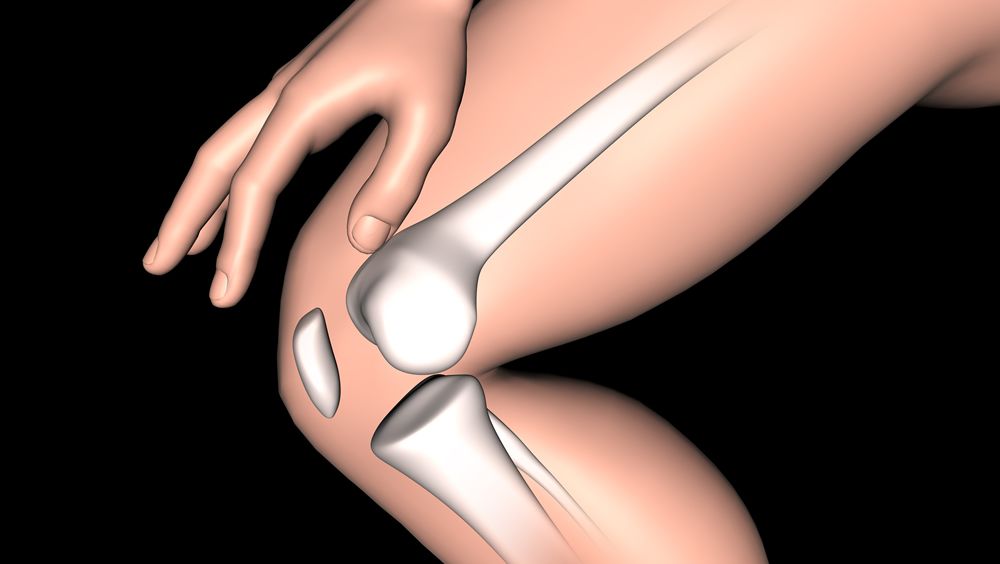

El exceso de óxido nítrico (NO) en el cuerpo está involucrado en la artritis reumatoide y otras enfermedades inflamatorias. Reducir la cantidad de este puede llevar a un nuevo enfoque terapéutico para una variedad de condiciones.

Ahora, investigadores de la Universidad de Ciencia y Tecnología de Pohang en Corea del Sur, han desarrollado un nanogel de eliminación del óxido nítrico y lo han probado en ratones con artritis reumatoide con resultados prometedores.

Así, el nanogel se ha comparado con el fármaco dexametasona de uso común, y ha demostrado ser mucho mejor para frenar la aparición de la artritis reumatoide, lo que apunta a la posibilidad de estudios en humanos en un futuro próximo.